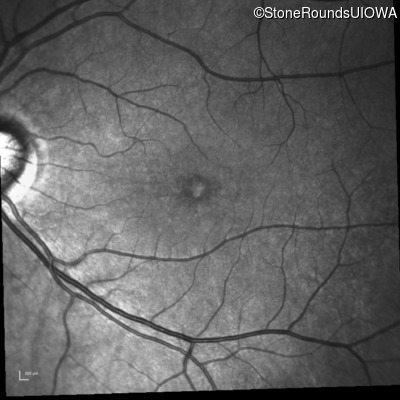

Infrared Fundus Photograph - Left - 20/40

Exemplar